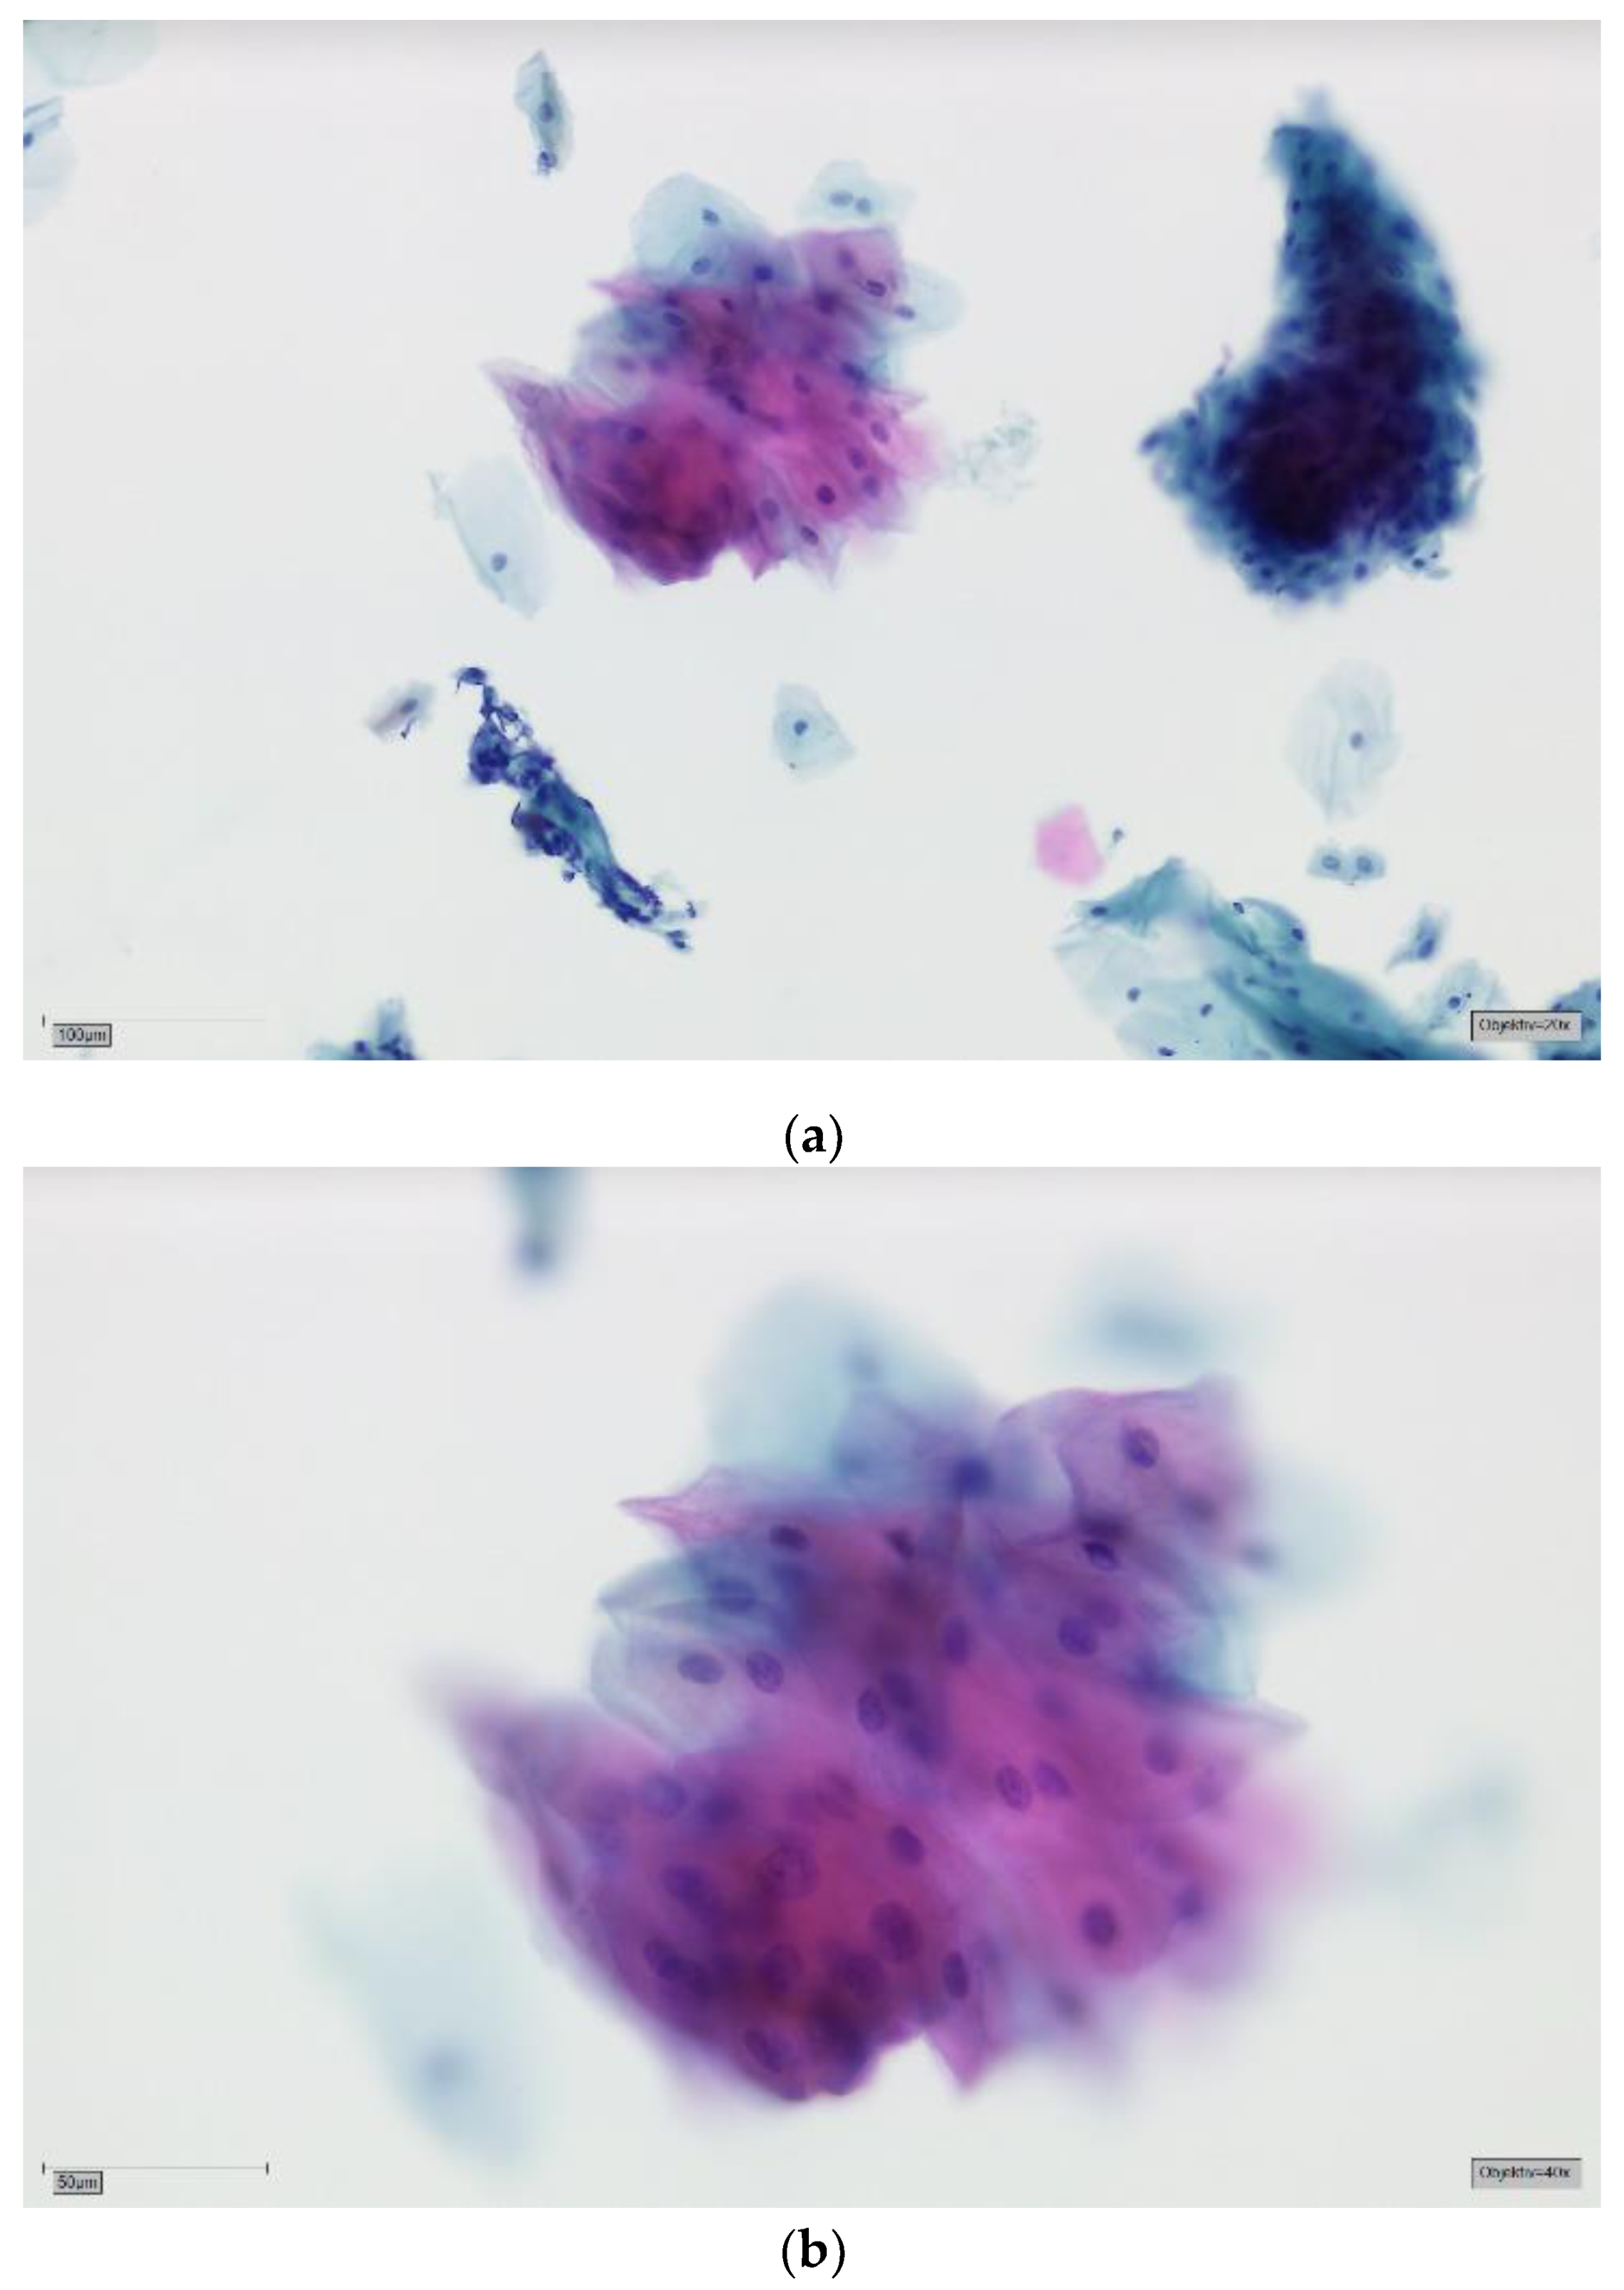

- Burkhardt, A.; Schwarz-Furlan, S. Abrasive cytohistology of squamous epithelial lesions. Transl. Res. Oral Oncol. 2018, 3, 1–11. [Google Scholar] [CrossRef] [Green Version]